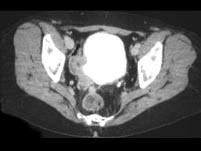

男,56岁,请根据所示图像,选择最可能诊断 ( )A、右侧输尿管乳头状瘤B、右侧输尿管癌C、膀胱结核D、右侧输尿管结核E、膀胱癌

问题 男,56岁,请根据所示图像,选择最可能诊断 ( )

选项 A、右侧输尿管乳头状瘤 B、右侧输尿管癌 C、膀胱结核 D、右侧输尿管结核 E、膀胱癌

答案 B